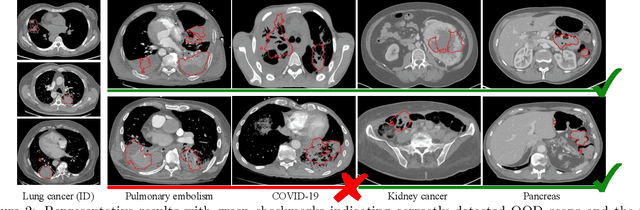

Abstract:Accurate segmentation of cancerous lesions from 3D computed tomography (CT) scans is essential for automated treatment planning and response assessment. However, even state-of-the-art models combining self-supervised learning (SSL) pretrained transformers with convolutional decoders are susceptible to out-of-distribution (OOD) inputs, generating confidently incorrect tumor segmentations, posing risks for safe clinical deployment. Existing logit-based methods suffer from task-specific model biases, while architectural enhancements to explicitly detect OOD increase parameters and computational costs. Hence, we introduce a plug-and-play and lightweight post-hoc random forests-based OOD detection framework called RF-Deep that leverages deep features with limited outlier exposure. RF-Deep enhances generalization to imaging variations by repurposing the hierarchical features from the pretrained-then-finetuned backbone encoder, providing task-relevant OOD detection by extracting the features from multiple regions of interest anchored to the predicted tumor segmentations. Hence, it scales to images of varying fields-of-view. We compared RF-Deep against existing OOD detection methods using 1,916 CT scans across near-OOD (pulmonary embolism, negative COVID-19) and far-OOD (kidney cancer, healthy pancreas) datasets. RF-Deep achieved AUROC > 93.50 for the challenging near-OOD datasets and near-perfect detection (AUROC > 99.00) for the far-OOD datasets, substantially outperforming logit-based and radiomics approaches. RF-Deep maintained similar performance consistency across networks of different depths and pretraining strategies, demonstrating its effectiveness as a lightweight, architecture-agnostic approach to enhance the reliability of tumor segmentation from CT volumes.

Abstract:Accurate detection and segmentation of cancerous lesions from computed tomography (CT) scans is essential for automated treatment planning and cancer treatment response assessment. Transformer-based models with self-supervised pretraining can produce reliably accurate segmentation from in-distribution (ID) data but degrade when applied to out-of-distribution (OOD) datasets. We address this challenge with RF-Deep, a random forest classifier that utilizes deep features from a pretrained transformer encoder of the segmentation model to detect OOD scans and enhance segmentation reliability. The segmentation model comprises a Swin Transformer encoder, pretrained with masked image modeling (SimMIM) on 10,432 unlabeled 3D CT scans covering cancerous and non-cancerous conditions, with a convolution decoder, trained to segment lung cancers in 317 3D scans. Independent testing was performed on 603 3D CT public datasets that included one ID dataset and four OOD datasets comprising chest CTs with pulmonary embolism (PE) and COVID-19, and abdominal CTs with kidney cancers and healthy volunteers. RF-Deep detected OOD cases with a FPR95 of 18.26%, 27.66%, and less than 0.1% on PE, COVID-19, and abdominal CTs, consistently outperforming established OOD approaches. The RF-Deep classifier provides a simple and effective approach to enhance reliability of cancer segmentation in ID and OOD scenarios.